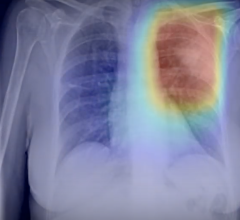

September 23, 2020 — RADLogics announced that the company’s novel AI-powered chest X-ray pneumothorax application has ...